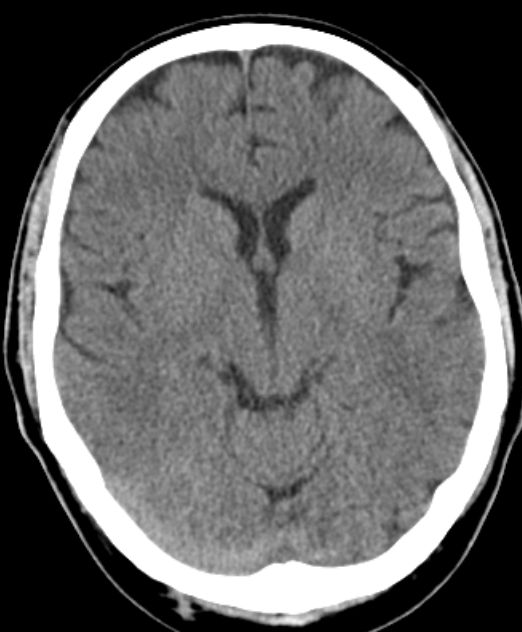

Kalotte |

46-jähriger Mann, der sich vor 6 Wochen am Hinterkopf gestoßen habe. Die Schwellung sei nicht zurückgegangen. Er habe zusätzlich Kopfschmerzen bekommen.

Das CT zeigt lediglich eine Füllung des Liquprspaltes links dorsal.Der Befund erwies sich DLBCL, welches die Dura infiltriert hatte. ![]() |